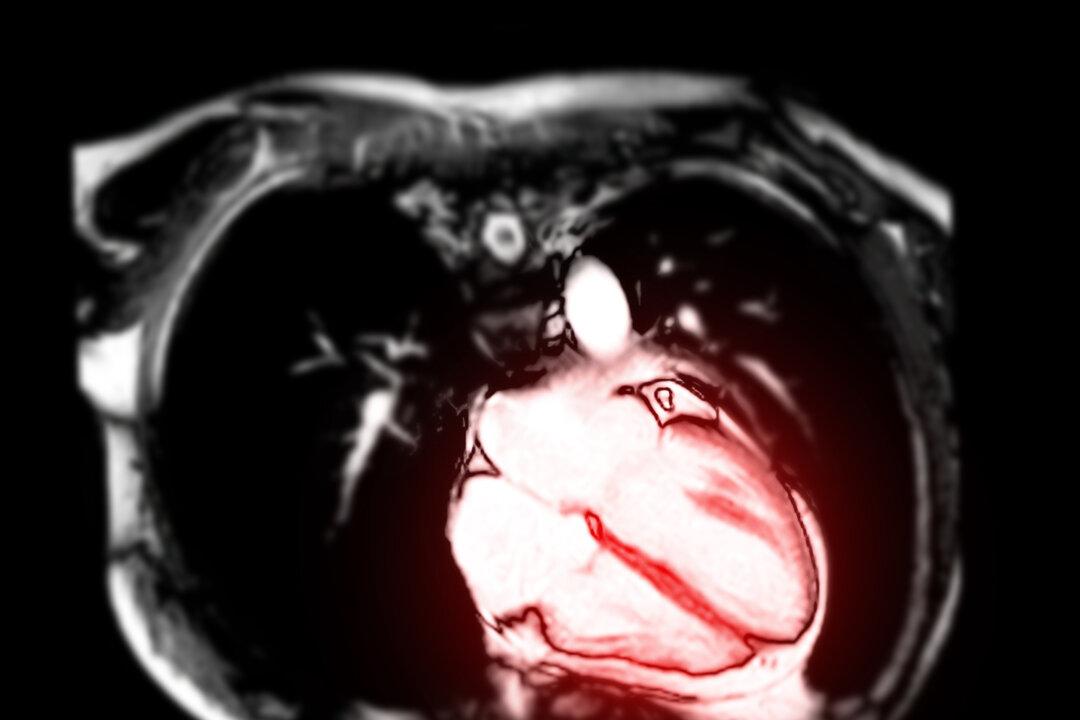

Magnetic resonance imaging of the heart Radiological imaging/Shutterstock